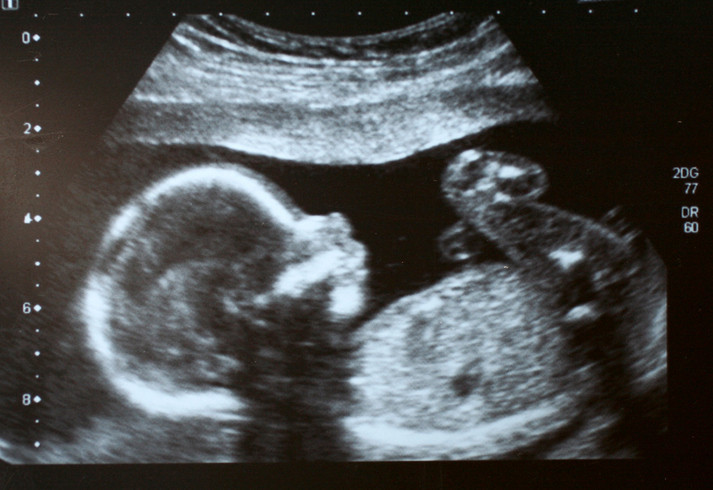

Gebelik zaten başlı başına hassas bir süreçtir ve yanlış ya da eksik bilgiler bu dönemi gereksiz yere daha zor hale getirebilir. Burada önemli bir denge var. Sadece endişe nedeniyle tedaviden kaçınmak, bazen ilacın kendisinden daha fazla risk yaratabilir.

Gebelikte ateşin kontrol altına alınmaması ya da şiddetli ağrının tedavi edilmemesi hem anne hem de bebek açısından olumsuz sonuçlara yol açabilir. Bu nedenle 'hiç kullanmamak daha güvenlidir” yaklaşımı her zaman doğru değildir.